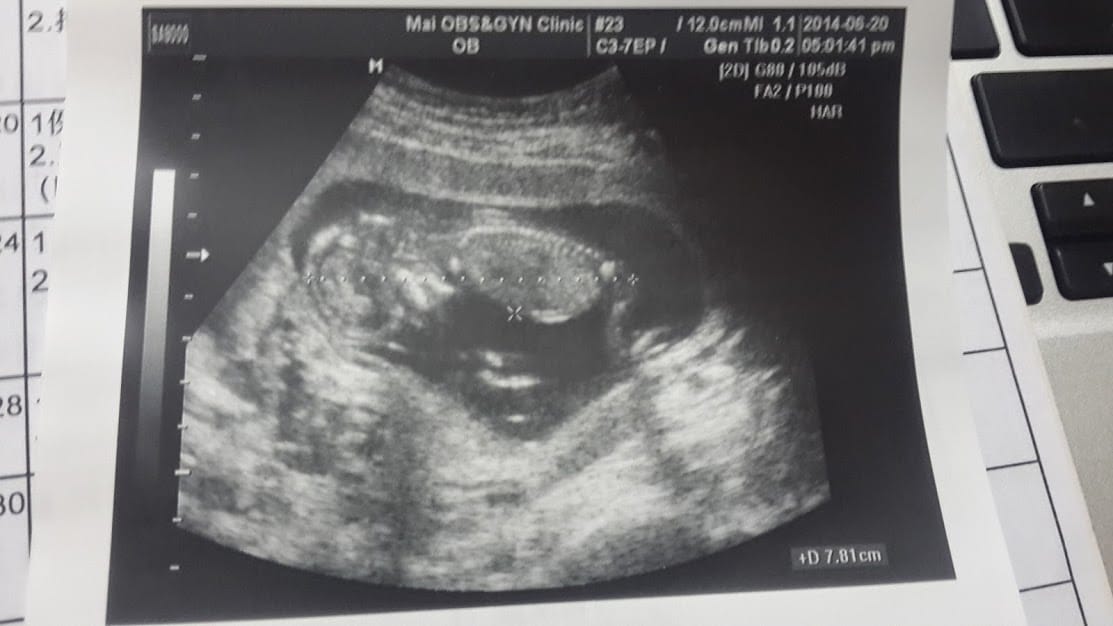

接著,成型了

聽到心跳的那一刻,我安心了

9W。第一次產檢

9W,畢竟還是好小好小一隻,雖然查資料時有孕吐表示有孕吐現象通常代表懷孕的結果還不錯,可是這次我還是很小心,

曾經有過一次空胚胎的的經驗,非常害怕聽不見胚胎心跳的那一剎那